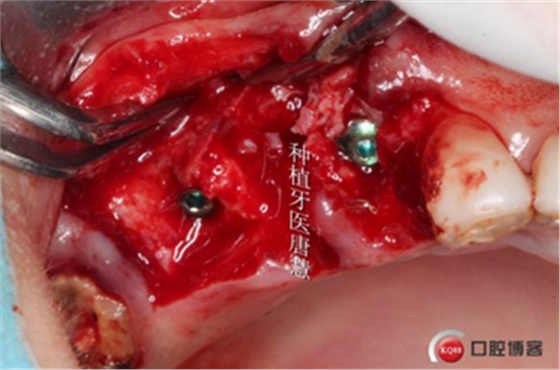

植入植體

自體骨填充拔牙窩與植體間空隙

植入骨粉